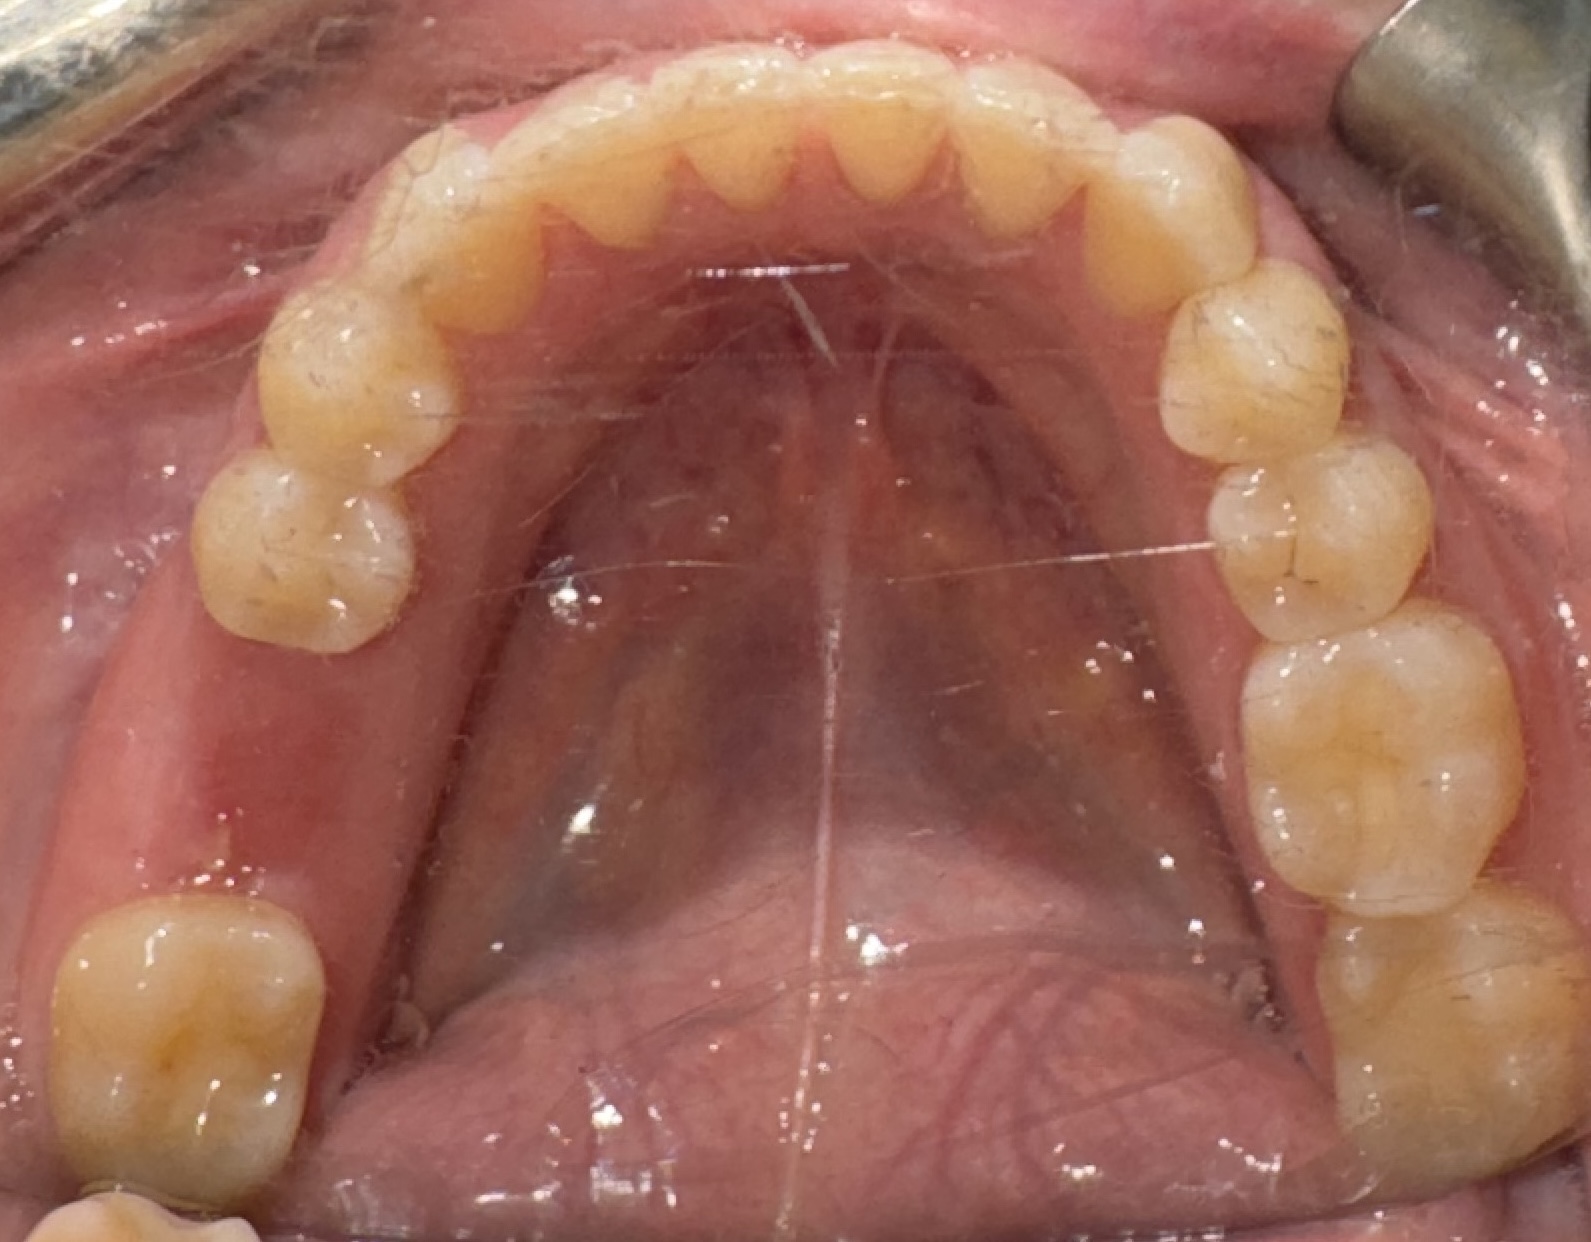

Visual Case Progression

All clinical images are shown at a consistent size for easy comparison.

Jennifer experienced full functional and aesthetic restoration of her molar region with no complications. Her final crown placement integrated seamlessly with her bite, and full chewing function was restored.